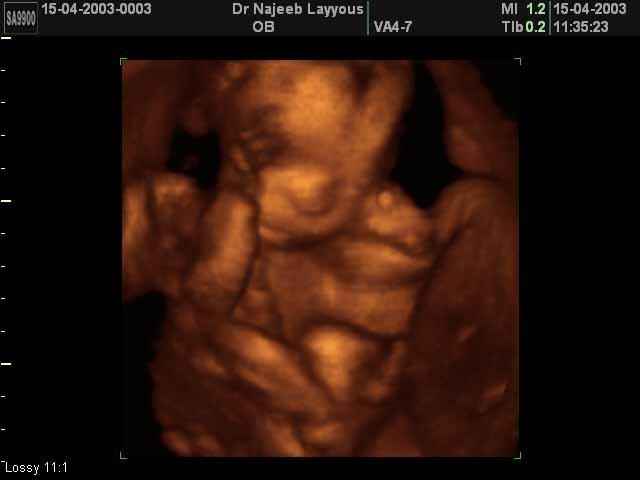

- 3D Fetal Profile Ultrasound Scan Photos

3D Second Trimester Ultrasound Scan Photos-second part of pregnancy | Dr N Layyous